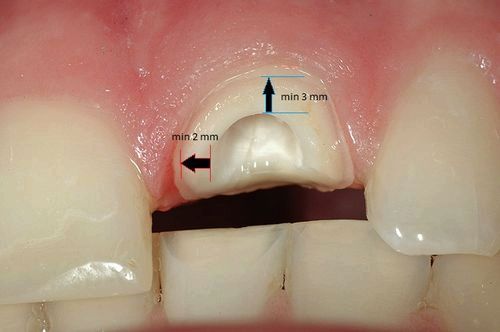

Що ж робити, якщо зуб зламався? Видаляти його? Або його можна буде відновити? І, якщо можна, то як це зробити краще? Основний критерій, за яким лікар приймає рішення про доцільність збереження "пенька", це кількість і якість твердих тканин, що піднімаються над яснами. В ідеалі це має бути так: краю зуба по всьому периметру вище рівня ясен, висота стінок не менше 2-3 мм, товщина не менше 1-2 мм.

При цьому чим вище і товщі стінки, тим краще прогноз для реставрації. Якщо ж скол стінки зуба стався глибоко під ясна, то такі зуби часто доводиться видаляти. Тому що ніяку конструкцію з хорошим прогнозом на такі зуби не сделать.Еслі цим правилом знехтувати, то в самому найближчому майбутньому ми отримаємо щось на зразок цього.